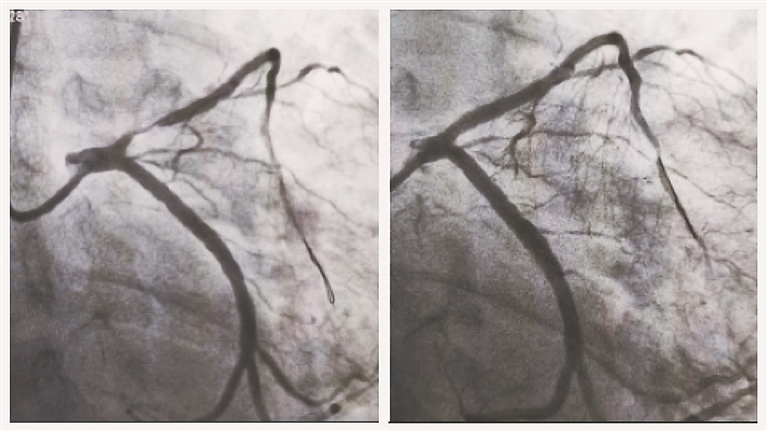

前不久,王先生在家人的陪同下来到哈尔滨市第二医院复查,称近一个月总感觉活动时有胸闷、气短等症状。哈尔滨市第二医院心血管内三科张国春主任对其进行详细问诊后,得知王先生在冠脉支架治疗几个月后就将吸烟、喝酒“捡了起来”,也不按时服用药物。张主任随即为王先生进行了造影检查,结果显示,王先生的冠脉支架内已严重狭窄。张主任认为,针对此情况,药物涂层球囊这种新的介入治疗技术是非常适合王先生的治疗手段。通过手术,医生帮王先生冠脉支架内再次狭窄的部位恢复了畅通,整个手术过程大约半小时,术后无任何并发症。

“药物涂层球囊扩张技术是最近几年推广起来的新型介入治疗方法,与再置入支架相比,药物涂层球囊无金属网格残留,从而减轻了血管内膜的炎症反应,降低了血管内血栓形成风险,治疗效果明显。”张主任介绍。